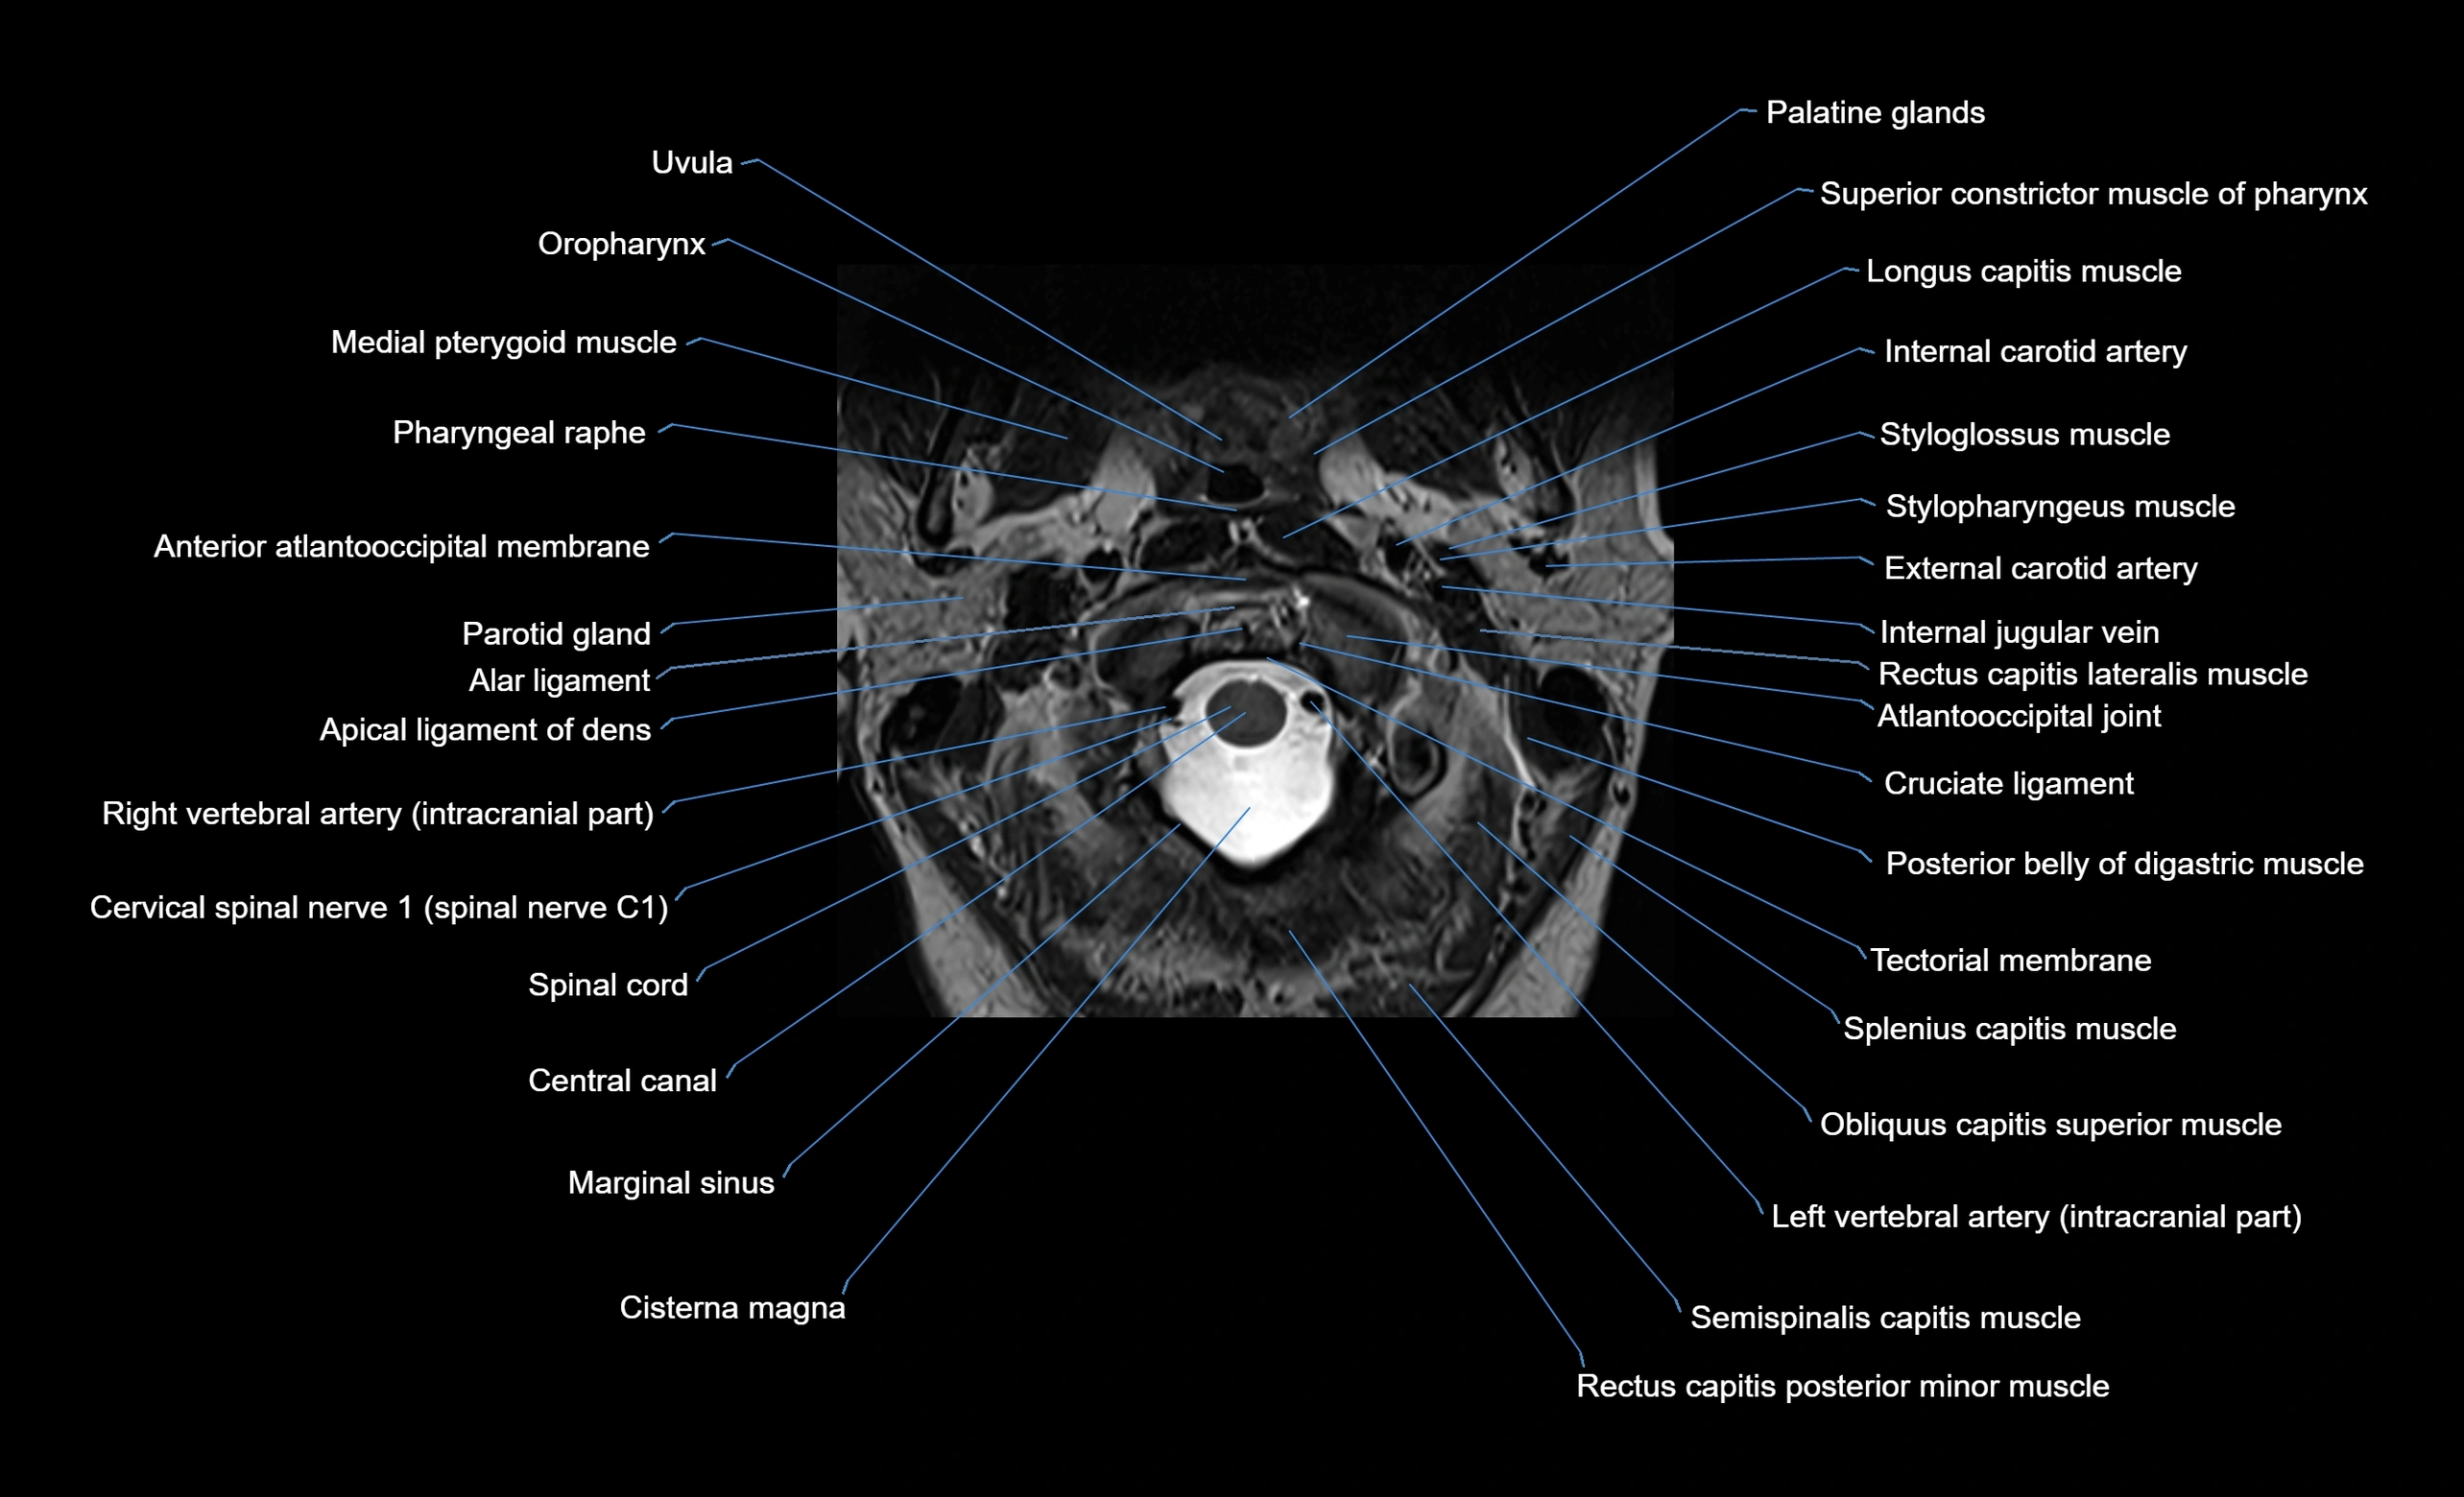

MRI appearance

T1-weighted images:

• Annular epiphysis: Low signal cortical rim at the vertebral margin

• Adjacent marrow: Intermediate-to-high signal in the vertebral body

• Disc interface: Clear delineation between bone and annulus

T2-weighted images:

• Annular epiphysis: Low signal intensity line

• Endplate cartilage (in younger patients): Intermediate signal

• Intervertebral disc: High signal nucleus pulposus

STIR:

• Annular epiphysis: Low signal cortical rim

• Adjacent marrow: Suppressed fat signal with preserved bony outline

• Utility: Highlights marrow and endplate interface in developing spine

MRI image

image